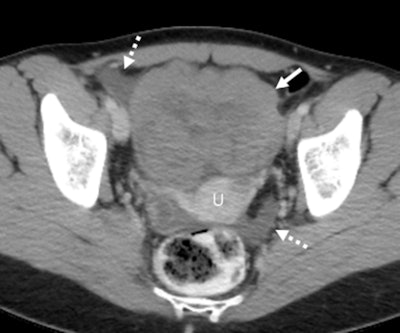

Axial contrast-enhanced CT scan in a 28-year-old premenopausal woman shows an incidentally detected solid-appearing left ovarian lesion (solid arrow) anterior to the uterus (U), associated with trace ascites in the right adnexa and cul de sac (dashed arrows). At pathologic analysis, this was shown to be ovarian dysgerminoma. Two readers misdiagnosed this lesion, one as a leiomyoma and one as an ovarian fibroma.Axial contrast-enhanced CT scan in a 28-year-old premenopausal woman shows an incidentally detected solid-appearing left ovarian lesion (solid arrow) anterior to the uterus (U), associated with trace ascites in the right adnexa and cul de sac (dashed arrows). At pathologic analysis, this was shown to be ovarian dysgerminoma. Two readers misdiagnosed this lesion, one as a leiomyoma and one as an ovarian fibroma. RSNA